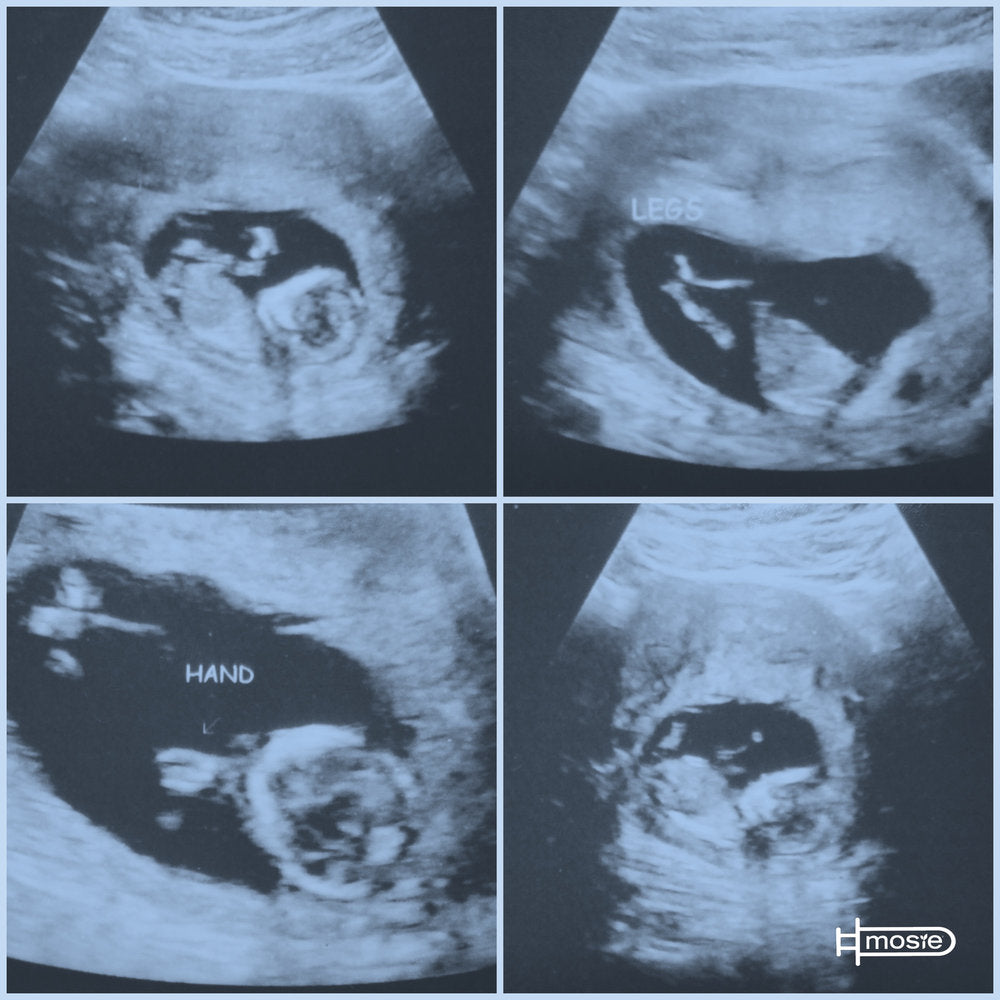

I went home that night and purchased a Mosie kit and we went for it. We had kinda watched BM cycle the month before so we had an idea of when to try: and hey we got two so we could try again if we were a little off. Following Maureen's instructions we waited, well i guess we didn't have to wait very long because two-ish weeks later (Oct 22) we got a +++++POSITIVE. BM is 24 weeks prego and we couldn't be happier!

A process we thought would be long and grueling turned out to be fast, easy, and comfortable not only for me, but for BM also. We both want to thank you Marc and Maureen from the bottom of our hearts for taking the complication out of this. For making it possible for people like us; that never even imaged it to be possible to have children of their own have the chance to conceive. This is a dream come true THANK YOU MOSIE BABY!!!!